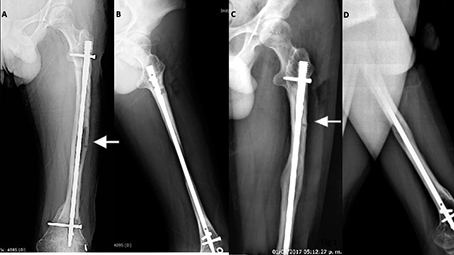

Figura 1. (A, B) Fractura diafisiaria fémur izquierdo, paciente masculino de 16 años, con OI tipo IV, después de 7 años de tratamiento con bifosfonatos. (C, D) Mismo paciente 2 años después con fractura diafisiaria proximal fémur izquierdo.

Figura 1